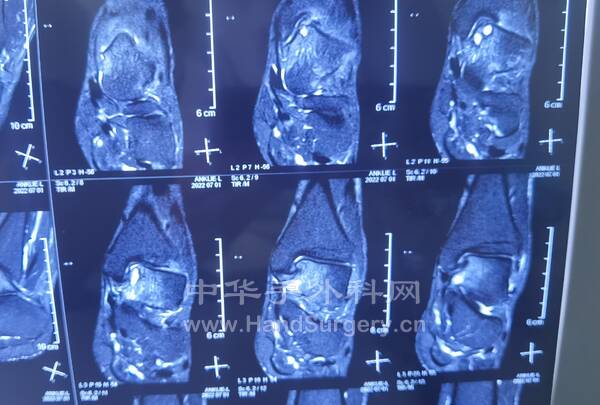

今日门诊女,38岁,距骨脱位,足下垂 诊断:术式:2022-6-29 15:30--19:50

1.跖筋膜松解

2.跟腱延长

3.胫前肌腱松解转位(固定在第三腓骨肌腱)

4.胫后肌腱和踇长伸肌腱松解

5.距下关节融合

6.环形外固定架固定

今日术后38天复查